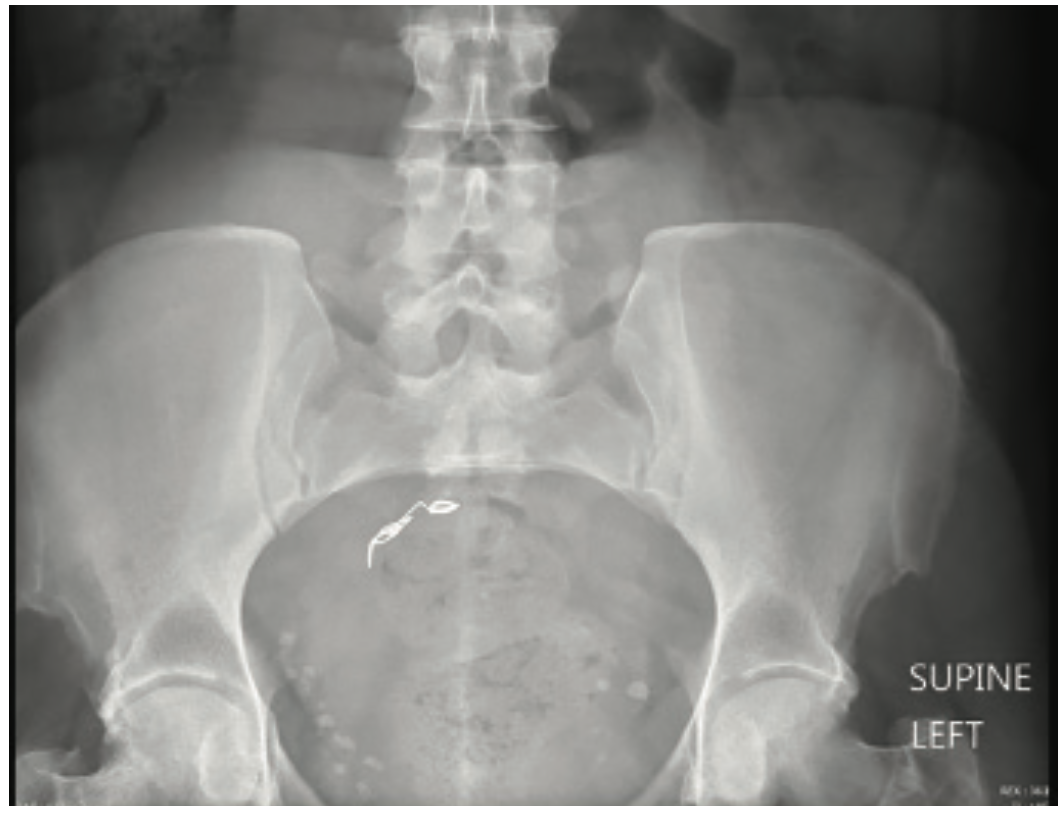

A 47-year-old woman with a medical history of hypertension and diabetes mellitus presented to the emergency department complaining of “something left in her heart.” Further history indicated that she had suffered from pelvic congestion syndrome and varicose veins in her legs, for which she underwent outpatient sclerotherapy and hypogastric vein embolization four days prior. Immediately after the procedure, coils dislodged from the performing instrument. Chest x-ray and a computed tomography chest scan revealed an approximately 11.7 mm coil located in the right atrium (Figures 1 and 2) and abdominal x-rays showed a coil implanted in the pelvis area (Figure 3). The patient was asymptomatic at that time. The day following her outpatient sclerotherapy and hypogastric vein embolization, coil retrieval via trans-jugular access was performed, but was unsuccessful even after a 5-hour attempt. The patient decided to come to our hospital emergency department (ED).